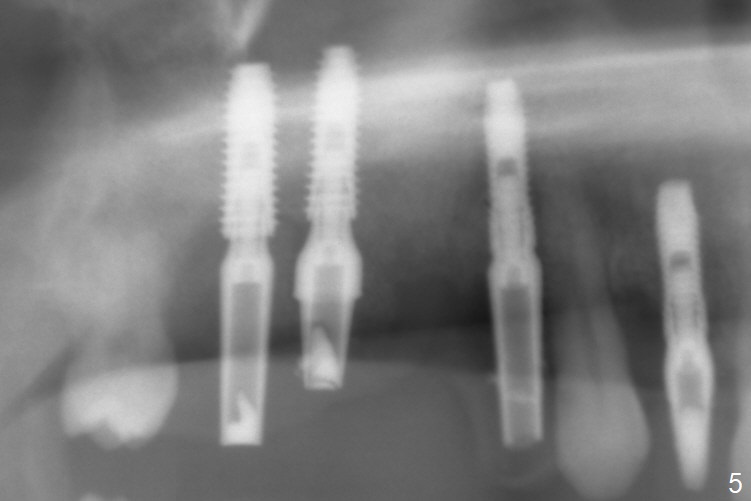

After extraction, the depths of initial osteotomy at #2, 3 and 5 are 13, 11.5 and 10 mm, respectively (Fig.1). Following adjustment of trajectory, a 3.8x13 mm UF implant is placed at #5 (Fig.2) with insertion of a 4.5x2 mm mill abutment as well as mineralized cortical/cancellous allograft (Vanilla, *). The mill abutment is chosen because the margin of a 5.5x7(5) mm cemented abutment is severely subgingival (Fig.4 at #3; ^ gingival margin). By the same token, a 4.5x3 mm mill abutment is placed at #2. In fact all of the 3 implants are placed 2-3 mm out of the bone (Fig.5). To prevent periimplantitis, abundant allograft is placed around the implants/abutments (Fig.2,4 *). Nearly 2 months postop, the mill abutment at #2 is adjusted for its height, while a 5.5x2.5 mm mill abutment is placed at #3 (Fig.6). To regain the buccal gingiva, the buccal margin of the provisional is shortened (Fig.6,7). Two weeks later, the gingival regrowth is not obvious (Fig.8 (nearly 3 months postop)). Local poor oral hygiene remains. A provisional FPD is fabricated. If his occlusion is normal for another 2 weeks, impression will be taken for upper (or UL) permanent restoration.